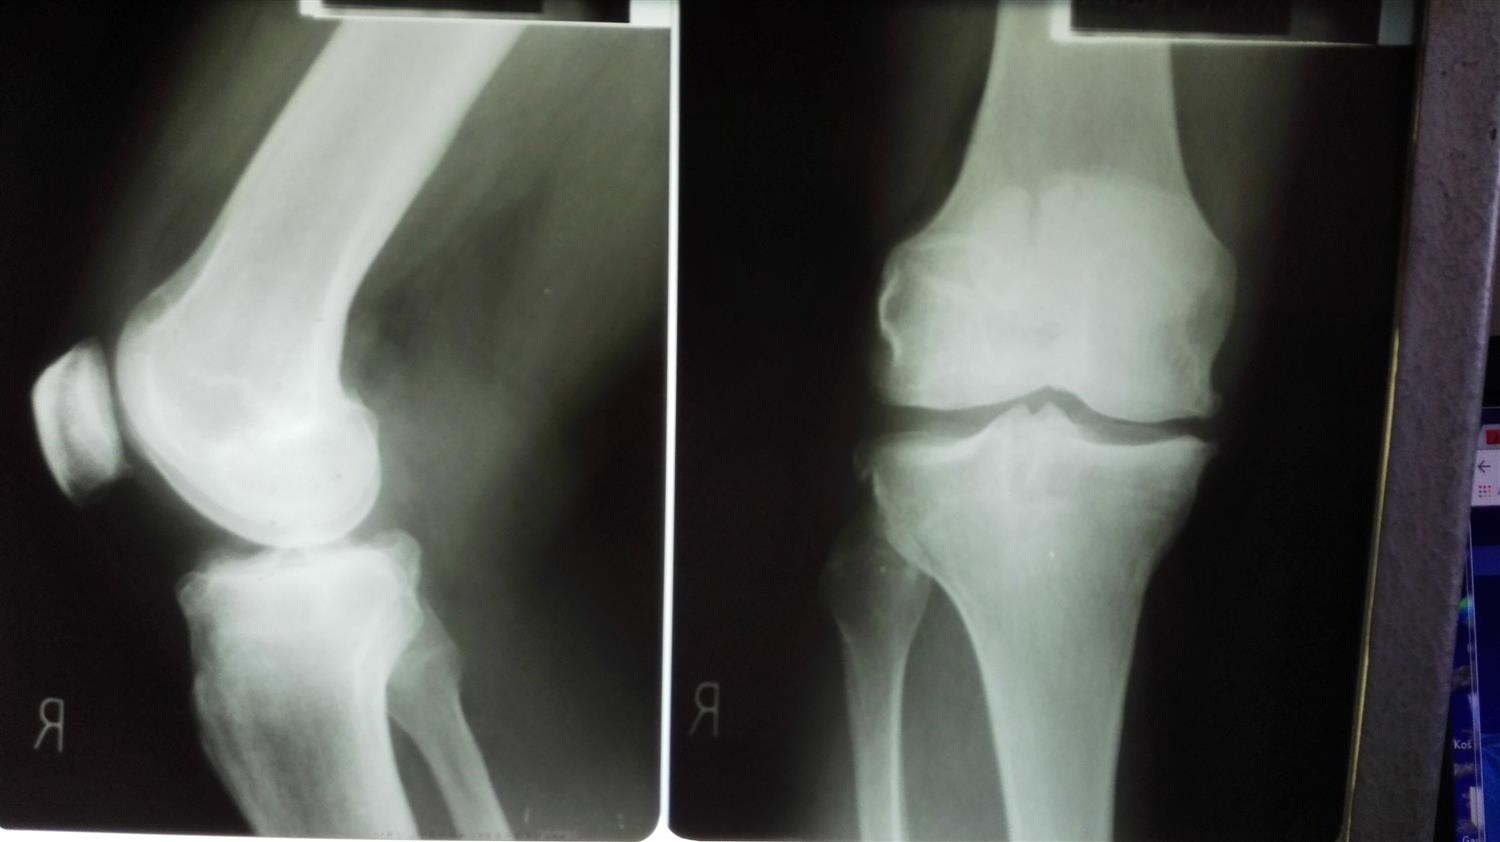

Nuclear Resonance of Right Knee that Shows Baker Cyst Baker's Cyst Torn Meniscus a baker's cyst may occur as a result of an injury to the knee, such as a tear in a meniscus, or damage to the cartilage. symptoms and causes. The most obvious symptom of a baker cyst is the bump that. However, some of the symptoms of a baker cyst are similar to. They typically result from a. Baker's Cyst Torn Meniscus.